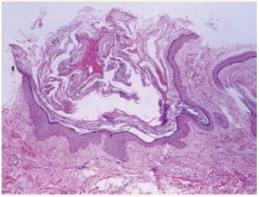

epitelio discretamente atrófico e hiperpigmentación de la capa basal, así como disminución de las glándulas sebáceas. En la dermis se observaron fibrosis discreta e infiltrado inflamatorio leve perivascular, con predominio de linfocitos y vasos capilares sanguíneos dilatados (Figuras 4y5). La correlación clínico-patológica fue de nevo comedón

Figura 4 Imagen histológica del nevo comedónico. Se observan las dilataciones foliculares que corresponde a comedones. HE40X.

En la histopatología se observan múltiples in-fundíbulos foliculares agrupados, dilatados y cubiertos con queratina lamelar, basófila y ortoqueratósica y epitelio atrófico. Las paredes del folículo están comprimidas por numerosas capas de queratinocitos y la epidermis interfolicular es papilomatosa e hiperqueratósica.1),(4 En la base de las invaginaciones foliculares pueden observarse glándulas sebáceas rudimentarias.6 Mediante microscopia electrónica puede observarse au-mento en el número de células de Langerhans y abundantes tonofilamentos en la porción supe-rior del estrato espinoso. El músculo pilo-erector muestra partículas intracelulares de glucógeno y no está completamente diferenciado.6 En análisis inmunohistoquímicos se ha demostrado aumento de la expresión del antígeno nuclear de proliferación celular, de la molécula de adhesión intercelular tipo 1, del antígeno de histocompa-tibilidad HLA-DR y la glucoproteína CD68, en la epidermis del infundíbulo piloso alargado y dilatado o en las células de la dermis más cer-cana al bulbo en proliferación.3